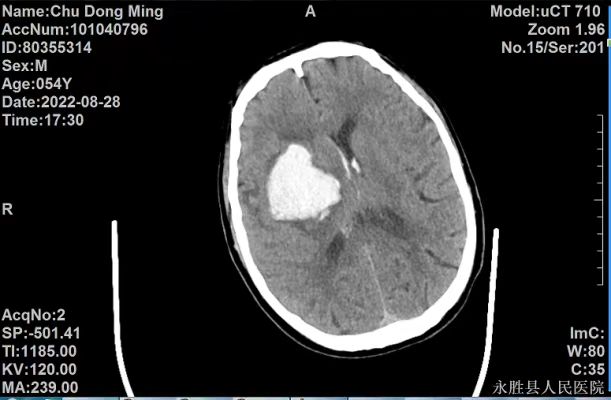

病例一:患者,男性,54岁,因“突发言语不清,意识模糊伴左侧肢体活动障碍5小时余”入院。入院后CT检查示:右侧基底节区急性大量脑出血,出血破入脑室系统,右侧侧脑室受压、中线结构向左移位。入院后诊断为:1.右侧基底节脑出血并破入脑室;2.脑疝形成;3.高血压3级,很高危组。患者病情危重,随时可能出现呼吸心跳骤停死亡,葛主任得知情况后迅速赶到医院,指导科室立即为患者实施开颅血肿清除术,手术顺利。目前患者正在做康复治疗。

术前

术后